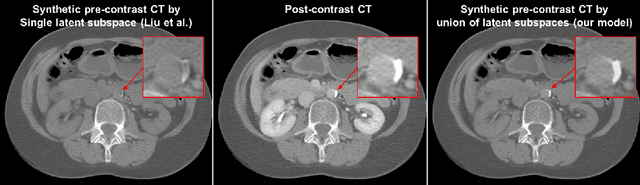

Abstract:Current deep learning based segmentation models often generalize poorly between domains due to insufficient training data. In real-world clinical applications, cross-domain image analysis tools are in high demand since medical images from different domains are often needed to achieve a precise diagnosis. An important example in radiology is generalizing from non-contrast CT to contrast enhanced CTs. Contrast enhanced CT scans at different phases are used to enhance certain pathologies or organs. Many existing cross-domain image-to-image translation models have been shown to improve cross-domain segmentation of large organs. However, such models lack the ability to preserve fine structures during the translation process, which is significant for many clinical applications, such as segmenting small calcified plaques in the aorta and pelvic arteries. In order to preserve fine structures during medical image translation, we propose a patch-based model using shared latent variables from a Gaussian mixture model. We compare our image translation framework to several state-of-the-art methods on cross-domain image translation and show our model does a better job preserving fine structures. The superior performance of our model is verified by performing two tasks with the translated images - detection and segmentation of aortic plaques and pancreas segmentation. We expect the utility of our framework will extend to other problems beyond segmentation due to the improved quality of the generated images and enhanced ability to preserve small structures.

Abstract:Calcified plaque in the aorta and pelvic arteries is associated with coronary artery calcification and is a strong predictor of heart attack. Current calcified plaque detection models show poor generalizability to different domains (ie. pre-contrast vs. post-contrast CT scans). Many recent works have shown how cross domain object detection can be improved using an image translation model which translates between domains using a single shared latent space. However, while current image translation models do a good job preserving global/intermediate level structures they often have trouble preserving tiny structures. In medical imaging applications, preserving small structures is important since these structures can carry information which is highly relevant for disease diagnosis. Recent works on image reconstruction show that complex real-world images are better reconstructed using a union of subspaces approach. Since small image patches are used to train the image translation model, it makes sense to enforce that each patch be represented by a linear combination of subspaces which may correspond to the different parts of the body present in that patch. Motivated by this, we propose an image translation network using a shared union of subspaces constraint and show our approach preserves subtle structures (plaques) better than the conventional method. We further applied our method to a cross domain plaque detection task and show significant improvement compared to the state-of-the art method.